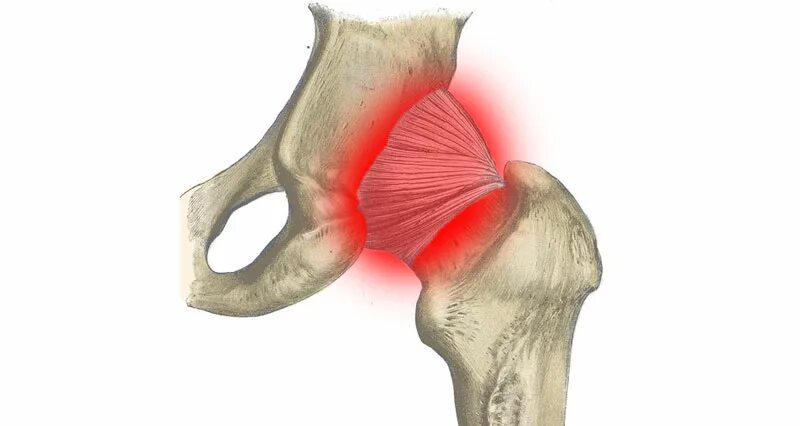

Как лечить синовит тазобедренного сустава